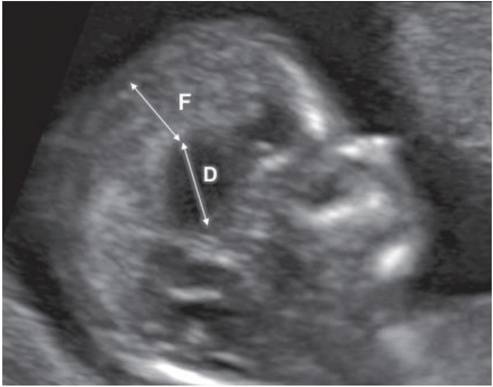

Multiplanar fetal neurosonography is the best imaging test to evaluate the fetus from the 20th week of gestation onwards. Most brain abnormalities remain undiagnosed until midway through the first trimester, and may go undetected due to small fetal brain structures. Between the 11th and 13th weeks, ultrasound can highlight changes that are incompatible with life. Multiplanar neurosonography is indicated in the middle of the first trimester of pregnancy, including non-axial plane scanning. The sonographer's knowledge of fetal anatomy and sonoembryology results in early diagnosis (Figure 2).10,16

Figure 2 Agenesis of corpus callosum in midsagittal ultrasound view in first trimester, showing increased ratio between diencephalon (D) and falx (F) diameters. In 80% of fetuses that had agenesis of the corpus callosum diagnosed later in gestation, there was an increased ratio between the diencephalon diameter (from midbrain to falx, including third ventricle and thalami) and the falx diameter. Adapted from Volpe et al. 2021.

In the first trimester it is therefore not possible to suspect callosal agenesis based on the lack of its direct visualization on grayscale ultrasound imaging. However, some authors have proposed seeking indirect signs of callosal absence at 11–13 weeks. In 80% of fetuses that had agenesis of the corpus callosum diagnosed later in gestation, there is an increased ratio between the diencephalon diameter (from midbrain to falx, including third ventricle and thalami) and the falx diameter. This sonographic marker seems to reflect early in gestation the upward displacement and dilatation of the third ventricle, which is commonly noted in the midtrimester in fetuses with absent corpus callosum.